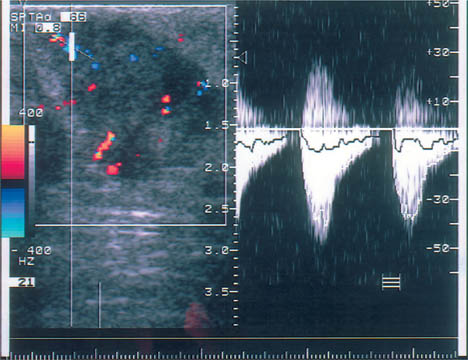

19 Doppler Ultrasound The vascularization of malignant tumors is a phenomenon well known from pathologic, biochemical, and angiographic studies, and we know that the degree of neovascularization correlates with the biologic behavior of the tumor. Thermography, once widely used as an adjunct to clinical examination, can detect the change in surface temperature associated with the focal increase in blood flow to a breast malignancy. However, it has been discredited as a screening method for breast cancer because of its low sensitivity, poor specificity (inflammatory processes as well as cancer are associated with local heat), and lack of precise anatomic localization (Williams et al., 1990). Contrast-enhanced MRI is also based on angiogenesis in malignant tumors as well as other factors such as membrane permeability. For many cancers, but certainly not all, there is an intense rapid rise followed by signal washout after the administration of a paramagnetic contrast agent, most commonly a gadolinium chelate such as gadopentate dimeglumine. The measurement of tumor blood flow is more applicable to lesion characterization than to screening. But there are anatomic situations that hamper evaluation of the breast tissue, and there are tumors that do not display typical diagnostic features, and the measurement of tissue blood flow can be helpful in evaluating problem cases of this kind. It should be understood, however, that the measurement of tumor blood flow is a nonspecific assessment that cannot differentiate lesions with absolute confidence. The degree of blood flow correlates with tissue metabolism. Thus, while fast-growing malignancies generally have a copious blood supply, blood flow is also increased in proliferative benign tumors, in pregnancy and lactation, and in inflammatory conditions. Doppler ultrasound has been used for more than 20 years to analyze blood flow in breast tumors. Initially only continuous-wave (CW) Doppler systems were available. These devices are very sensitive, but they require an experienced user and it is difficult to examine nonpalpable lesions. Pulsed Doppler systems became popular in the early 1980 s, as they allow for selective flow sampling in vessels that are located by ultrasound imaging. Tumor vessels are very small, however, and usually cannot be visualized in the B-mode image. It is tedious to move the Doppler sample volume through the image while searching the tumor and its surroundings for blood vessels. Also, most of the older duplex scanners used a low frequency and were relatively insensitive in detecting tumor vessels. As a result, duplex scanning did not find significant applications in tumor diagnosis. Color flow imaging paved the way for the use of Doppler ultra-sound in tumor diagnosis. The first instruments had poor sensitivity. By the 1990 s, however, color Doppler technology had advanced sufficiently to permit the effective localization of tumor vessels (Fig. 19.1). This was achieved through the use of higher Doppler frequencies and improved signal processing. The recording of Doppler spectra was also improved and provides additional information on tumor blood flow (Fig. 19.2). Nevertheless, color Doppler demonstrates only a portion of the vessels. This is due to the limited sensitivity of Doppler in detecting microscopically small vessels and the dependence of the Doppler principle on the beam–vessel angle. Vessels that are perpendicular to the beam direction are poorly detected. Blood flowing in the direction of the beam results in a higher frequency shift and a better recorded signal. Fig. 19.1 Color Doppler image of invasive ductal carcinoma. The greatest vascular density is found at the periphery of the tumor. Note the predominantly radial pattern of vessels converging on the tumor. The high sensitivity setting, with a PRF of 800 Hz, often leads to aliasing in the vessels due to the high flow velocities. This must be tolerated, since increasing the PRF would decrease Doppler sensitivity and reduce the number of detectable vessels. Fig. 19.2 Color Doppler and duplex sonography for the measurement of blood flow. Again, most vessels are found at the tumor periphery. The Doppler spectrum shows a high systolic blood flow velocity (37.9 cm/s) and an absence of flow in diastole (RI = 1.0). This high resistance pattern is typical of breast carcinoma. Breast carcinomas often have a firm consistency, exerting a pressure that collapses the blood vessels within the tumor. As a result, only peripheral vessels can be seen in most cases and the flow resistance is high. To improve the visualization of small vessels and avoid the problem of insonation angle, a different method of signal processing was developed. This technique, called power Doppler, does not register the angle-dependent frequency shift but the intensity (amplitude) of the reflected signals, which depends on volume flow. As a result, the course of tumor vessels is more clearly visualized (Fig. 19.3 a, b). This technique is susceptible to artifacts, however, and much experience is needed to interpret the images correctly. Another disadvantage is that, for the present, power Doppler imaging yields nonquantitative information. The image is interpreted subjectively, and there are no objective parameters that can be used for tumor differentiation. For these reasons, color Doppler is still preferred. It is easily combined with duplex technology for concomitant flow imaging and flowmetry. However, this requires a sensitive instrument with optimum settings. Given the range of variation among different instruments, standardization is difficult to achieve. In our previous studies at the University of Freiburg, we used the ATL UM9 HDI (Philips Medical Systems, Bothell, WA) color flow imager with a 10–5-MHz linear-array transducer. We used a 50–100 Hz filter and a pulse repetition frequency (PRF) of 800–1000 Hz. The power and gain were set as high as possible, that is, just below the noise level. Doppler ultrasound is used to investigate focal abnormalities rather than to scan the entire breast. Given the variability of tumor blood flow, all vessels should be sampled for the quantitation of flow. Because vessels often are not visualized within malignant tumors, particular attention should be given to feeding vessels that enter the periphery of the mass. With just enough pressure to maintain contact, the transducer should be placed lightly on the breast to avoid vascular compression. Before any vessels are sampled, various insonation angles should be tested to obtain an optimum Doppler signal. First a slow scan through the tumor is done in the color Doppler mode so that all the vessels can be located and counted. Then the examination is completed by analyzing flow signals in the duplex mode. Usually the course of the vessels can be seen, and so the probe angle can be adjusted to ensure an accurate measurement of flow velocity. Duplex analysis should include the determination of maximum systolic velocity (S) and end-diastolic velocity (D). This provides information on total blood flow and makes it possible to calculate indices from the Doppler spectra. The most important index to be determined is usually the resistance index (RI) or the AB ratio: RI = (S – D)/S AB ratio =S/D The pulsatility index (PI) is less frequently determined because it requires fitting an envelope curve to the Doppler spectrum. This is time-consuming and fraught with potential errors. Our comparative measurements have shown, moreover, that this index correlates closely with the RI and the AB ratio. Flow velocity analysis provides a basis for various calculations. For example, the vessel with the highest-velocity flow can be used for tumor differentiation. It is also possible to calculate the mean value for all the flow velocities measured in a particular tumor. Because carcinomas are supplied by many small, low-flow vessels in addition to a few large vessels, the mean velocity may be low despite a high total blood flow. A better way to assess total blood flow is to add together all the flow velocities measured in the tumor. It would be simpler and more accurate to use a computer to extract the total blood flow from the color Doppler data. Fig. 19.3 a, b Color Doppler and power Doppler images of a solid cellular carcinoma. The relatively soft consistency of this tumor accounts for the central vascular density. a Branching vessels can be identified in the color Doppler image. b The course of the vessel is seen somewhat more clearly in the power Doppler image, but individual vascular branches are not defined. Malignant tumors are associated with an increased number of blood vessels (Fig. 19.1, Table 19.1), which converge on the tumor and enter it in a radial pattern. Often, however, only vessels at the tumor periphery are visualized while vessels inside the tumor are collapsed as a result of the very firm consistency of most carcinomas. Although the vessels in malignancies often communicate through shunts and do not have a muscular coat, the hard tumor consistency leads to a high flow resistance (Fig. 19.2). Even so, the flow velocities in most tumor vessels are increased but are highly variable. The same applies to the Doppler spectra that are sampled from the vessels.